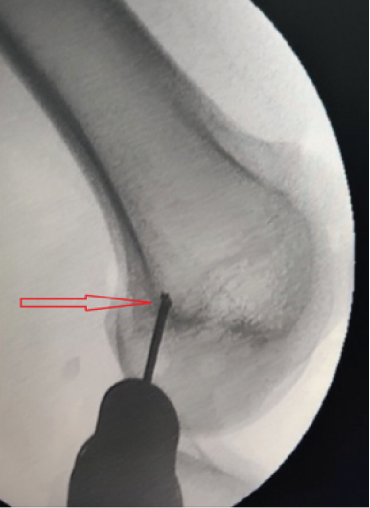

①在大腿上绑扎止血带。进行诊断性关节镜检查,以清除髌骨或股骨外侧髁上任何松动的骨软骨体。处理其他关节内病变,并评估髌骨轨迹[图1]。

⑧通过关节镜观察移植物,确认其处于滑膜外的位置,并且髌骨轨迹稳定情况令人满意[见图8]。

图8:通过关节镜观察到的移植物——如图中圆圈所示,其处于滑膜外的位置。